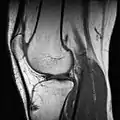

Применяются физикальные методы исследования: осмотр, пальпация, а также сбор анамнеза. Из инструментальных методов для визуализации изменений анатомических структур сустава большое распространение получило МР-исследование. Для оценки целостности и структуры костей, формирующих сустав, предпочтение отдаётся рентгенографии и компьютерной томографии. В настоящее время для диагностики применяют также артроскопию.

МРТ коленного сустава.